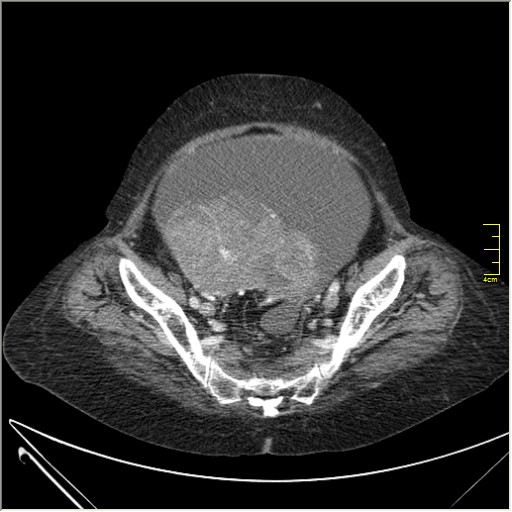

Женщина 72 года. Поступила с жалобами на вздутие живота. После осмотра хирургом, была сразу направлена на КТ брюшной полости.

Итак, асцит с объёмным образованием таза. В данном случае можно быть более конкретным, у пациентки неоплазия правого яичника с региональной лимфаденопатией (увидели?) и выраженным асцитом, характерным именно для злокачественных опухолей яичников. Пациентка оперирована ( операция Вертгейма); диагноз верифицирован: аденокарцинома правого яичника (серозная). Направлена к онкологу для дальнейшего лечения.